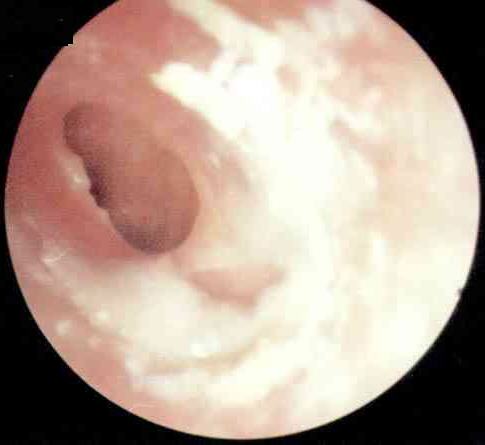

化脓性中耳炎